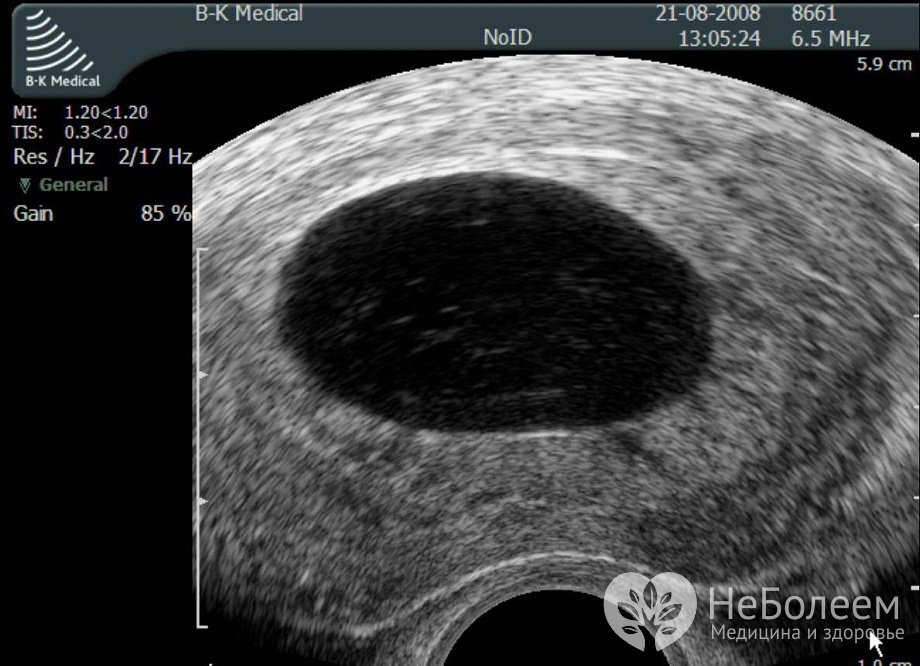

Выявить анэмбрионию можно на УЗИ начиная с 7 недели беременностиПодтвердить диагноз анэмбрионии возможно только по результатам ультразвукового исследования полости матки. На эхограмме определяется плодное яйцо, в котором отсутствуют желточный мешок и эмбрион. Учитывая вероятность диагностической ошибки, женщине рекомендуют повторить ультразвуковое исследование через 7–10 дней. Только если и в ходе этого исследования не будет обнаружен эмбрион, ставят окончательный диагноз анэмбрионии.